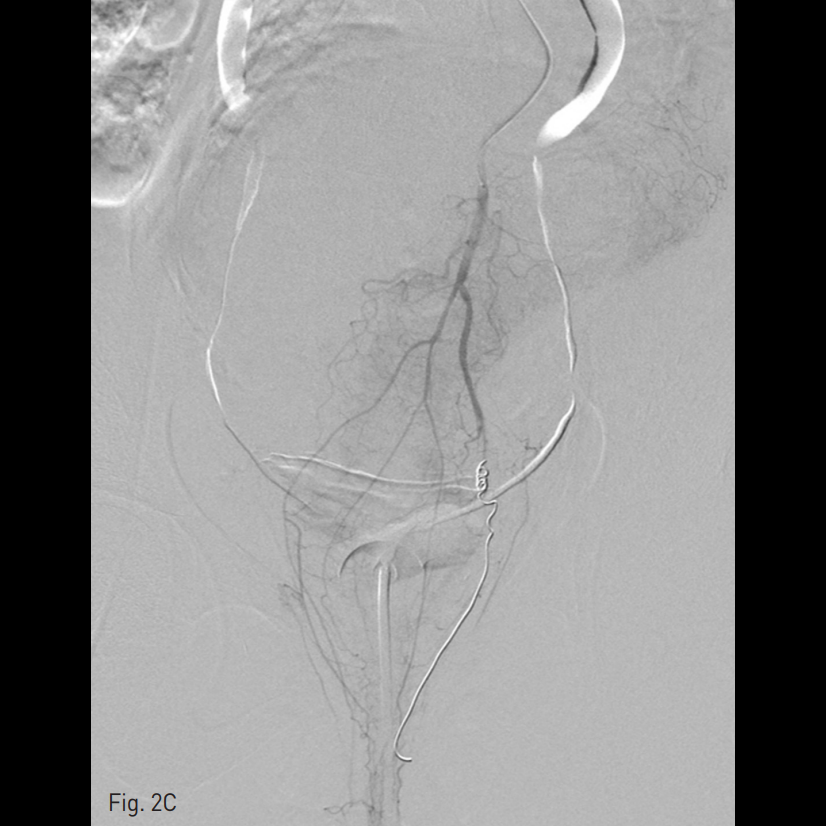

우측 총대퇴동맥을 천자하여 5 Fr sheath를 삽입하고, 5 Fr RUC catheter (Roberts Uterine Catheter, COOK medical, Bloomington, IN, USA)를 이용하여 좌측 내측 장골동맥을 선택하여 조영술을 시행한 뒤 좌측 자궁동맥을 선택하여 조영술 시행하였으며 (Fig. 1A), 출혈의심소견이 있어 gelfoam을 이용하여 색전술을 시행하였다 (Fig. 1B). 이후에 시행한 우측 내측 장골동맥을 선택하여 조영술을 시행한 뒤 (Fig. 1C), 우측 자궁동맥을 초선택하여 조영술을 시행하였을 때, 우측 자궁동맥이 비후되어 있어, gelfoam을 이용하여 색전술을 시행하였다. 색전술 직후 산부인과 진찰에서 지속적인 출혈소견이 보였다. 이에 5 Fr pigtail catheter를 이용하여, 대동맥 조영술을 시행하였다. 하장간막동맥 (Inferior mesenteric artery)으로 부터 출혈 소견이 관찰되었다 (Fig. 2A). 이에 대해서 2.2 Fr 마이크로카테터 (Progreat, Terumo, Japan)를 이용하여 하장간막동맥을 초선택하여 코일(Nester microcoil, COOK Medical, Bloomington, IN, USA)과 gelfoam (Spongostan, Ferrosan Medical Devices, Denmark)을 이용하여 색전술을 시행하였다 (Fig. 2B). 이후 다시 하장간막동맥 조영술을 시행하여 더 이상의 출혈이 없음을 확인하고 시술을 종료하였다 (Fig. 2C).

Fig. 2

C. Bleeding was controlled after coil embolization.